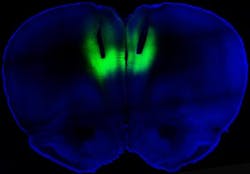

To test whether altering the activity in this brain region could impact addiction, Chen and his colleagues employed optogenetics to shut the activity on and off using a laser. First, they took light-sensitive proteins called rhodopsins and used genetic engineering to insert them into neurons in the ratâs prefrontal cortex. Activating this region with a laser tuned to the rhodopsins turned the nerve cells on and off. Turning on these cells wiped out the compulsive behavior, while switching them off turned the non-addicted ones into addicted, the researchers found.